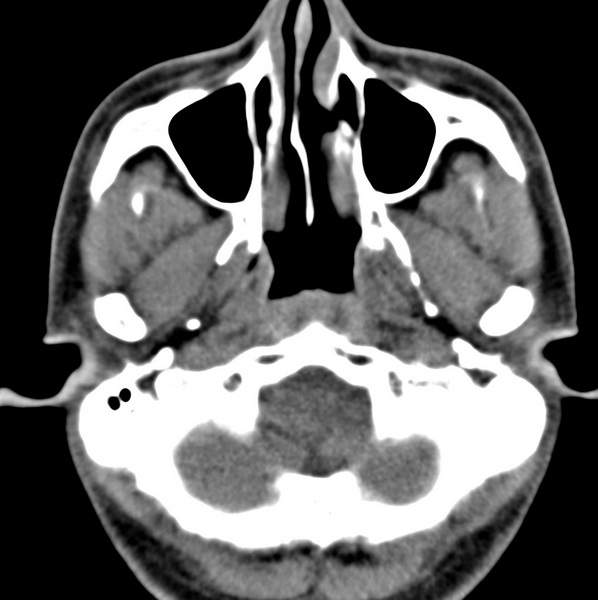

男、31、鼻咽部肿瘤放疗后请帮忙看看。

效果好,右侧破裂孔扩大,局部骨质缺损,为颅底骨质破坏。

1)鼻咽部肿瘤侵犯颅底放疗术后改变。2)左侧蝶窦炎。

咽后壁增厚,左侧咽鼓管隆突增大、咽鼓管咽口变浅,同侧咽旁间隙较窄。右侧颅底骨质破坏?为什么不在同一侧?

鼻咽部肿瘤侵犯颅底放疗术后改变.